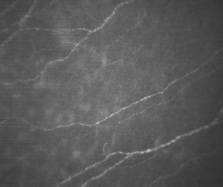

| The bulk of the cornea consists almost entirely of the corneal stroma, a

fibrous tissue layer approximately 450 μm thick in the central cornea (Fig. 14). As determined by biochemical and immunohistologic methods, the

stroma is composed predominantly of type I collagen with types III, V, and

VI also in evidence.34,37,48 Immunogold labeling was intense for collagen type VI, which is associated

with the interfibrillar matrix only and not localized to the striated

fibrils.48 Type III and V collagens are codistributed with striated type I collagen. This

codistribution is similar to the codistribution of types III

and V in Bowman's layer. Type V and III collagens also have been

labeled at the interfacial matrix separating stroma and Descemet's

membrane.34,48 Type I collagen is organized into striated fibrils 25 to 35 nm in diameter with periodic banding according to electron microscopy.46 Type V collagen appears colocalized with type I in the striated fibers.54 Using atomic force microscopy, corneal collagen was reported to have a D-periodicity of 63.9 to 68.5 nm.55,56 Scleral periodicity banding occurs at 67-nm intervals. Fibrils are composed of 4-nm microfibril components arranged in a right-hand helix and tilted at 15 degrees to the fibril axis in the cornea and 5 degrees in the scleral. This striated banding is the result of the offset, stacked arrangement of individual procollagen triple-helix molecules into units of five (the microfibril), which are further combined to form the basic unit of the collagen fibril. The 67-nm axial repeat was shown to correspond to the N– and C- telopeptids and the D-band periodic gap zone.57 These fibrils are combined into highly ordered, sheet-like bundles called lamellae, which lie essentially parallel to the corneal surfaces. Lamellae vary in width and thickness throughout the stroma, with a tendency to have smaller dimensions anteriorly (0.5 to 30 μm wide and 0.2 to 1.2 μm thick) and larger dimensions posteriorly (100 to 200 μm wide and 1 to 2.5 μm thick).46 Hundreds of individual lamellae can be discerned in a cross-sectional slice of the full-thickness central cornea. LAMELLAR ORGANIZATION Fibrils within a given stromal lamellae appear to run without interruption along the length of the lamellae presumably to become contiguous with scleral fibrils at the limbus. Normally occurring fibril terminations are observed only in association with extracellular compartments on the processes of fibroblasts in which collagen molecules are organized into fibril strands during stromal remodeling.58 Fibrils in adjacent lamellae tend to be oriented at highly oblique angles relative to one another. The orientation of lamellae as a function of depth has been well studied in the developing chick cornea in which the orientation is nearly orthogonal.59 There have been reports of nonrandom orientations of lamellae in the human. At midcentral stroma, lamellae tend to orient along the vertical and horizontal axes.60 In the far periphery evidence exists for circumferential annular orientation that is parallel to the limbus.61 Because it is impractical to track single bundles of fibrils for any great distance in the stroma, these fibrils may actually be organized with swirling arc-like orientations near the limbus that collectively appear to be a continuous belt of fibrils.62 Cross-sectional views of the central cornea give a first impression of a highly ordered structure with little interweaving among lamellae. Closer examination of the histologic evidence, combined with mechanical strength tests of lamellar organization, indicates that a much more complex network of interweaving and lamellar bifurcations does exist.63 In particular, the anterior one-third of the stroma appears more disorganized than the posterior two-thirds when seen with light microscopy. Similarly, the peripheral regions of the stroma are more disorganized than the central regions in the human, as shown by interlamellar cohesive strength tests and concomitant histology.63 Polarized light micrographs of relatively large expanses of the stroma in cross section reveal the extent of interweaving and bifurcation more readily.53 Some collagen fibril bundles are not truly lamellar but are oriented at oblique angles to the surface-parallel lamellae.53,63 These bundles also appear to bifurcate frequently, with portions becoming contiguous with surface-parallel lamellae at various depths. A measure of cohesive strength that structurally ties the anterior stroma to more posterior regions of stroma is imparted by these depth-varying fibril bundles. These oblique bundles have not been observed in rabbit stroma, which may account for the greater stiffness and shearing strength seen with isolated human stroma compared with the rabbit.2 However, when swollen stroma is examined in thick sections, fine collagen bundles are found between the lamellar bundles in the rabbit, but not in the human. In the corneas of the elasmobranchs, suture fibers oriented perpendicularly to the corneal surface are seen. These observations of depth-varying collagen in diverse species may indicate analogous structural features that resist shearing forces, but they are not homologous structures. PROTEOGLYCANS The hydrophilic mucopolysaccharide ground substance in which collagen fibrils are embedded takes the form of the proteoglycan, polypeptide protein cores to which glycosaminoglycans (GAGs) are covalently bonded. GAGs are large polysaccharide groups consisting of repeating disaccharide units, with glucosamine or galactosamine on the first monosaccharide and galactose, glucuroninc acid, or iduronic acid on the second monosaccharide. Proteoglycans can assume a wide variety of forms depending on the number and types of GAGs per molecule, as well as the inclusion of additional side chains such as oligosaccharides. Some of the GAGs found in the stroma are keratan sulfate, dermatan sulfate, chondroitin sulfate, chondroitin, and the atypical, noncovalently bound hyaluronic acid. A discussion about the complexity and subtle species distinctions of corneal proteoglycans is beyond the scope of this chapter, but the subject has been reviewed elsewhere.64,65 The most abundant corneal stromal proteoglycans are lumican with keratan sulfate GAG side chains and decorin with chondroitin/dermatan sulfate GAG side chains. In vitro analysis of fibril formation indicates that both lumican and decorin appear to have an inhibitory effect on collagen fibrillogenesis because of the core proteins of the PGs and not the GAG side chains.66 Keratan sulfate and dermatan sulfate GAGs appear to bind along the collagen fibrils at regularly spaced sites and tend to be oriented perpendicularly to the fibril. The less prevalent chondroitin sulfate and hyaluronic acid are localized within interfibrillar spaces without evidence of binding to the fibril collagen.67 In the developing cornea, proteoglycan-GAG complexes vary in distribution and orientation with time.67 The primary role of GAGs appears to be the maintenance of interfibrillar spacing. GAGs are heterogeneously dispersed throughout the cornea. Castoro and co-workers found dermatan sulfate to be more prevalent in the anterior portion of the bovine stroma, and keratan sulfate more prevalent in the posterior portion.68 This distinction was based on differential water content within the stroma. It was theorized that more total water was found in the posterior stroma because keratan sulfate readily absorbs and releases water. Conversely, the anterior stroma contained relatively less extractable water, presumably because dermatan sulfate GAGs bind to water molecules more tightly than do keratan sulfate GAGs. However, Klyce and Russell have shown that this anterior-posterior hydration gradient can be predicted entirely by consideration of the transport and permeability characteristics of the epithelium and endothelium.69 Borcherding and associates63 found a reduction of keratan sulfate at the corneal limbus of the human stroma with a corresponding rise in dermatan sulfate. Dermatan sulfate was not found centrally but was a major GAG within the sclera. Chondroitin was found centrally but not peripherally, while chondroitin sulfate was found only in the periphery and limbus.70 TRANSPARENCY Recently, Müller and colleagues71 reported that the distance between adjacent collagen fibrils is 20 nm on average, and given a fibril diameter of 23 nm, the interfibrillar spacing by her protocol using fresh, unswollen tissue is only 43 nm on average. They also found that the ring-like structures of proteoglycans surrounding each fibril (when viewed in cross section) have a mean diameter of 45 nm, while the distance between proteoglycans along the axial length of each fibril is 42 nm. Each proteoglycan has an average length of 54 nm based on her measurements and a thickness of 11 nm.71 The small, regular diameter of the individual collagen fibrils and their highly ordered spatial arrangement with interfibrillar spacing much smaller than that of visible light (400 to 700 nm) has been implicated as the basis for corneal transparency.72 In contrast, the sclera has collagen fibrils that are not uniformly arranged and have varying diameters, which results in an opaque tissue. Maurice72 recognized that because of the difference in refractive index between the stromal collagen fibrils and ground substance, up to 94% of incident light on the cornea would be scattered, making the cornea virtually opaque. He proposed that collagen fibrils are in a lattice-like arrangement with perfect dimensional order and that each fibril scatters an individual wavelet of light. By the process of destructive wavefront interference, the light scatter from individual fibrils would be cancelled by one another, and the cornea would remain transparent as long as the lattice arrangement was maintained. This theory is an example of long-range spatial order in which even fibrils relatively distant from one another are precisely spaced in accordance with the spatial dimensions of the lattice. Histologic views of the stromal fibrils in the normal cornea suggest that they possess a quasi-regular spatial arrangement with short-range interfibrillar order but not long-range order.73 It is generally believed that short-range order must be accounted for in any description of corneal transparency and light scatter because of the unique arrangement of the fibrils. Of the short-range order models, that of Hart and Farrell is among the most rigorous.73 In the case of physiologically induced light scatter, Benedek74 noted the histologic appearance of regions devoid of fibrils, which he called "lakes." Light scatter could be generated by a difference in the local refractive index of the stroma, for example by a pocket of localized edema, as compared to the surrounding tissue. Lakes were suspected to be artifacts of histologic processing, but Farrell and associates have shown that these lakes theoretically could induce light scatter equivalent to observed empiric data.75 This supports the theory that edematous light scatter is generated by lakes with critical dimensions approaching one-half wavelength of light and not merely by a random disruption of fibrillar order. However, models are subject to limitations, and edema may induce a continuum of disruption, including lakes and short-range order disruption. Also, Bowman's layer, which has randomly distributed fibrils, is transparent. The mechanisms responsible for this clarity appear to be the lack of scattering elements spatially arranged with dimensions that approach the critical distance of one-half wavelength of light and the fact that the overall thickness of the layer is relatively small compared to the stroma. KERATOCYTES Occupying 3% to 5% of the total stromal volume, keratocytes are interspersed throughout the corneal stroma and form a communicating network through their branching stellate processes. With confocal microscopy, keratocytes appear to be less densely dispersed than in Bowman's layer (Fig. 15). In the deep stroma, keratocytes appear spindle-shaped and more numerous than in the midstroma (Fig. 16). Tight junctions have been seen between tips of processes, although usually a 20-nm intercellular space is seen.21 Gap junctions are functional based on microinjections of fluorescent dyes that pass from cell to cell.76 Occasionally, portions of keratocyte processes appear to lie within a lamellar bundle; however, the majority of keratocytes reside within the potential interlamellar spaces. The stromal density of the keratocytes demonstrates a linear loss as a function of age, which tends to parallel the loss of endothelial cells over time.77 The keratocyte is approximately 2 μm thick at the cell body with a disproportionately large nucleus compared to its cytoplasmic volume. Free ribosomes, rough endoplasmic reticulum, and Golgi's complexes are found in the cytoplasm. Immunoelectronmicroscopic antigen labeling specific for types III, V, and VI collagen was found localized to keratocytes; however, type III labeling was weak.34,48 Keratocytes have a remarkable presence of a network of fenestrations on their cell walls that appear to be functionally related to the diffusion and mechanical attachment of collagen fibers to the cell body.78 Keratocytes are normally spatially quiescent, albeit constantly maintaining the extracellular matrix. They appear to have a clockwise, corkscrew-like appearance in terms of their distribution with depth in the stroma. It is speculated this has some function with respect to communication in depth, while maintaining optimum corneal transparency.78 However, keratocytes have a considerable degree of mobility; when activated they are able to migrate into wound margins rapidly to synthesize new collagen and glycoproteins for tissue repair. In vitro results indicate that a wide variety of growth factors increase keratocyte chemotaxis.79 A major difference between activated and quiescent keratocytes is the organization of the contractile cytoskeletal proteins. In the quiescent form, contractile proteins appear to be associated with f-actin for the maintenance of cell shape and interconnectivity. In the activated form, a putative contractile apparatus comprised of f-actin, myosin, and α-actinin is organized into muscle-like stress fiber bundles.80 Chondroitin sulfate and collagen types V and VI were shown to have an inhibitory effect on activated keratocyte migration, while fibronectin increased migration significantly. Integrins had a mediating effect on migration, presumably affecting cell–matrix interactions.81 Keratocytes can vacate the anterior stroma rapidly after de-epithelialization.82 The signal for this response is unknown, but the observation underscores the potential responsiveness of this usually unremarkable cell. When keratocytes do respond to a stromal insult, they are more appropriately termed fibroblasts to reflect the diminution in their stellate appearance and their increased ability to generate procollagen for subsequent fibril construction. There is strong circumstantial evidence that keratocyte activation is correlated to a higher level of reflected light scatter from the stroma, specifically from the cell bodies themselves, and this may constitute much of the haze observed after photorefractive keratectomy (PRK).83 It has been well documented that tears are cytotoxic to keratocyte cells, and it has been shown that apoptosis is reduced by surgical removal of the extraorbital lacrimal gland, although some compensatory cytotoxicity appears to be derived from the intraorbital lacrimal gland in the mouse model.84 Birk and Trelstad85 investigated the mechanisms and regulation of fibrillogenesis in embryonic chicken cornea. They found that extracellular fibroblast cell surface compartmentalization was responsible for the organization of the fibrils into lamellar bundles. Furthermore, the orthogonal organization of lamellae in the chick was due to the orthogonality of the surface compartments of the fibroblast processes. Fibroblasts apparently orient themselves during the deposition of the secondary stroma by taking spatial cues existing in the primary stroma. Thus, a single fibroblast cell is able to dispense bundles of collagen fibrils along axes that are oriented at or near 90 degrees to one another; these bundles then form into lamellae. |